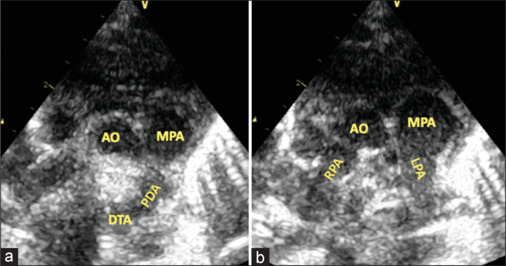

We describe a 7-day-old newborn who presented with arterial desaturation and respiratory distress. The evaluation showed a duct with a continuous right-to-left shunt and an anomalous origin of the right pulmonary artery from the aorta. We discuss the hemodynamics leading to continuous right-to-left ductal flow and the subsequent intraoperative evaluation that resulted in a successful single-stage surgical repair of this interesting case.